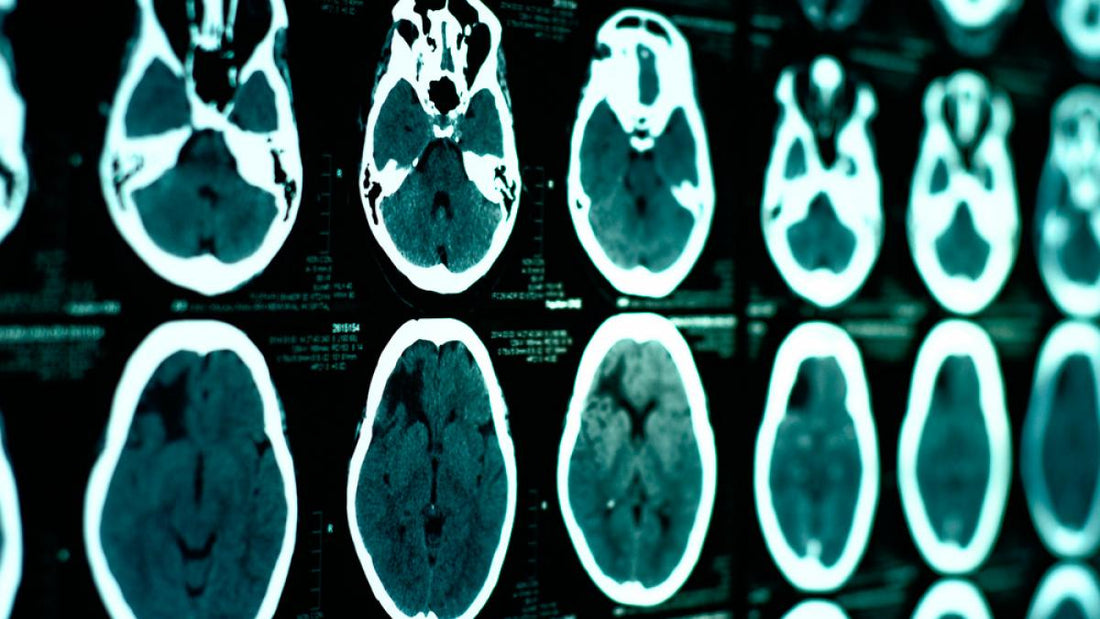

El diagnóstico temprano depende del trabajo conjunto de pediatras, ortopedistas, terapeutas físicos y ocupacionales. Son ellos quienes, mediante evaluaciones clínicas y estudios complementarios, pueden detectar signos de alerta y guiar a la familia hacia el tratamiento más adecuado.